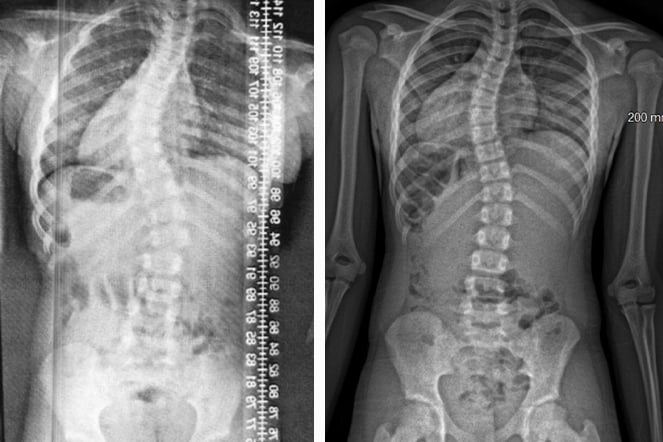

a before and after image of an x-ray featuring a spine

An X-ray image of Abagail's spine before and after years of dedicated bracing.

For the past four years, Clark has treated Abagail's scoliosis, working closely with the Shriners Children's Erie Pediatric Orthotic and Prosthetic Services team and Spinal Technology to design a custom anterior open Boston 3D brace specifically for her. Abagail’s physician, Stephen Mendelson, M.D., recognized that her severe double major curve, including a high thoracic curve, required a unique approach. He requested a brace that was both low profile and highly effective. Unlike traditional braces, the Boston-3D applies corrective pressure on the outer side of the curve while cutting out corresponding areas on the inner side, allowing the spine to shift in the desired direction. Thanks to Abagail’s dedication to wearing the brace and the customized design, her scoliosis curve has been reduced by more than 50%, an outcome that is rarely achieved.